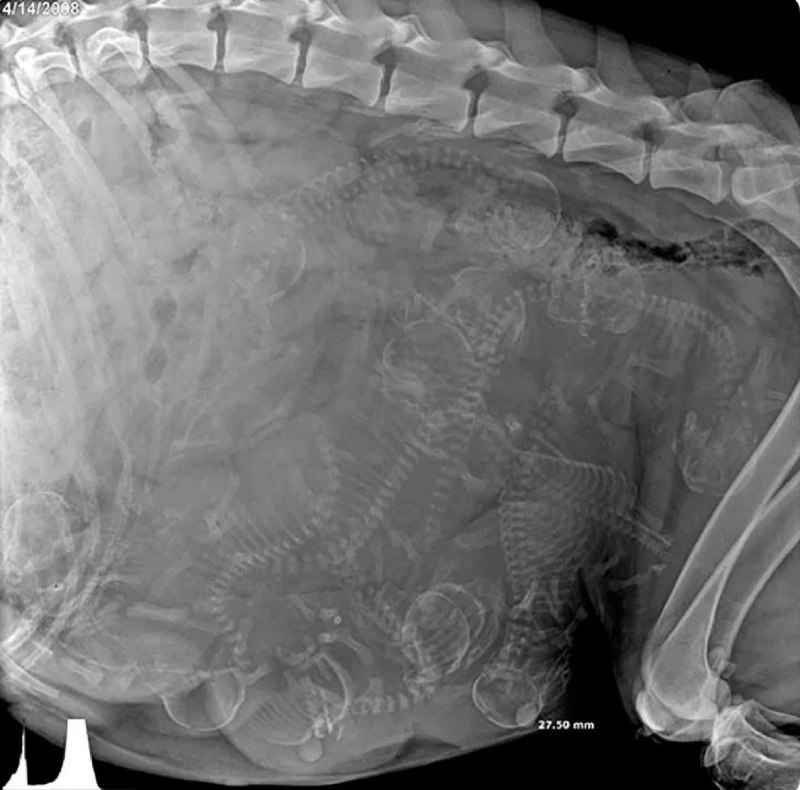

رادیولوژی یک سگ حامله

💬Clarence